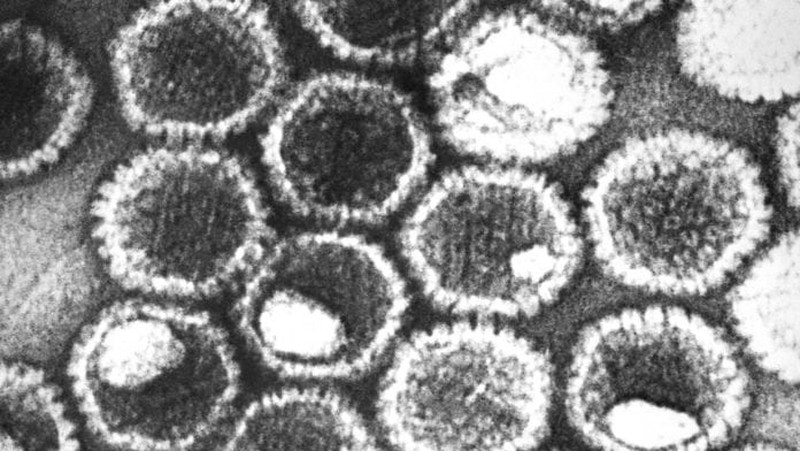

Kalau ini adalah tampilan dari virus influenza A tipe H5N1. Foto: Getty Images